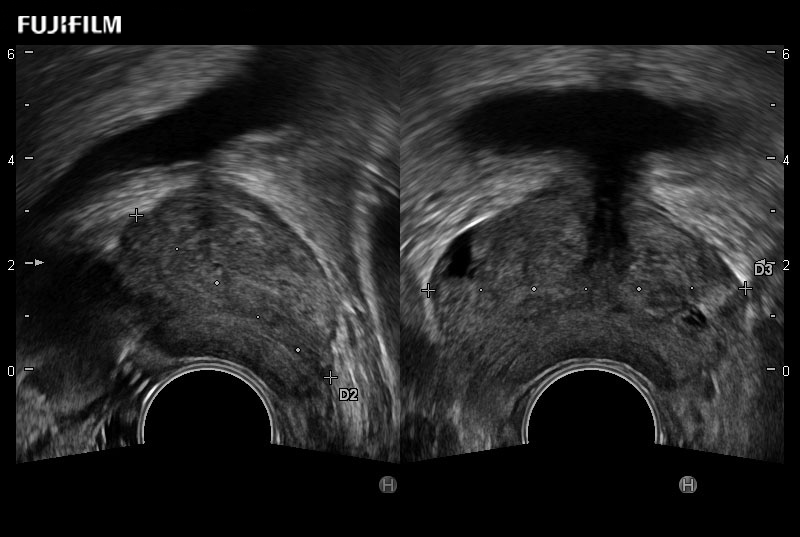

Ideal transducer for Transperineal Biopsy, Hydrogel Spacer Placement, Brachy LDR & HDR, Cryo, and MPMRI procedures.